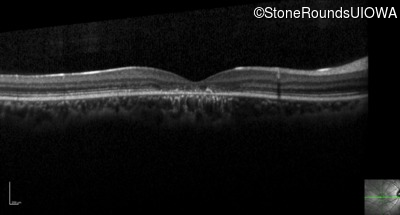

Optical Coherence Tomography - Right - 20/125 -2

Exemplar / OCT Stack